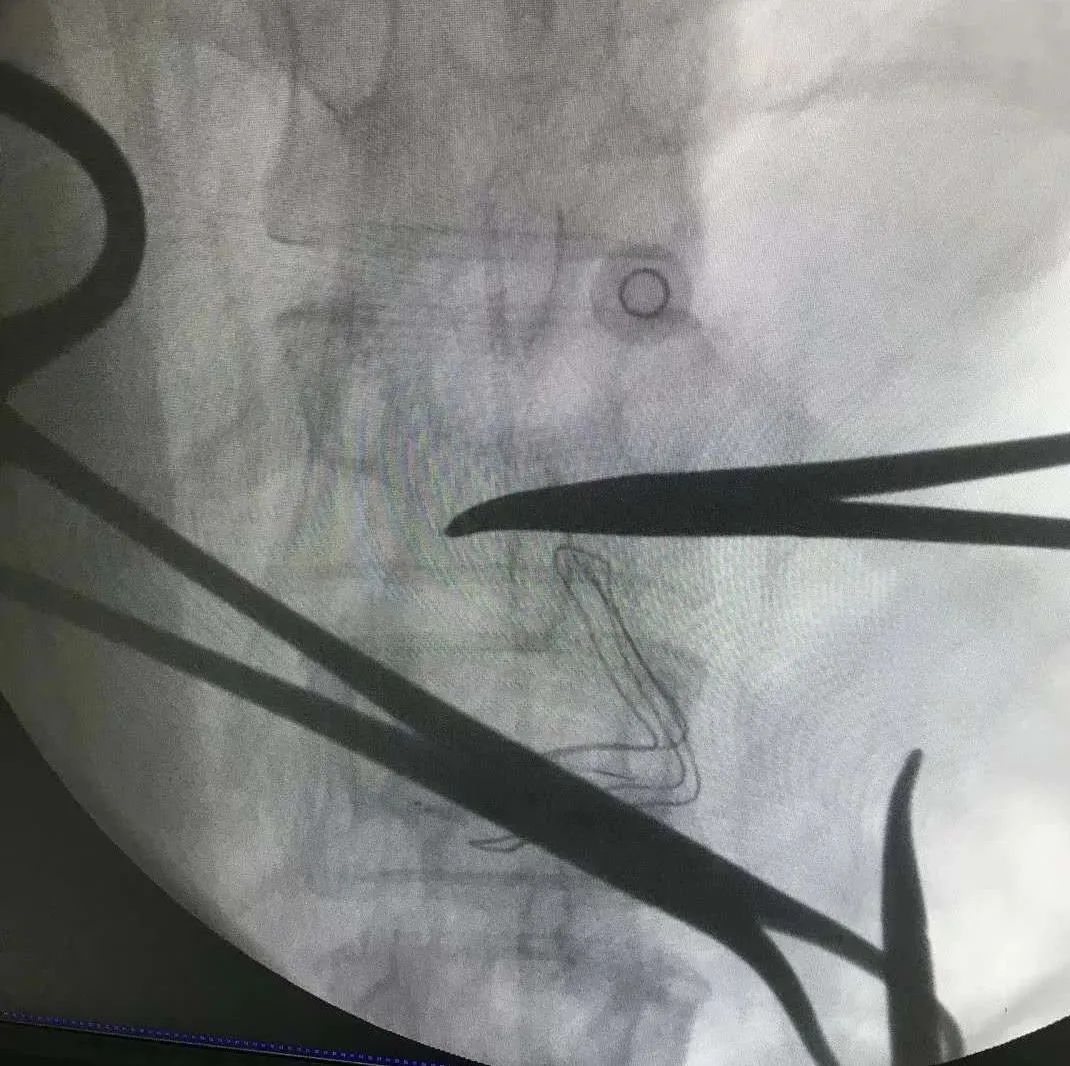

几经周折,尹女士来到了河南省肿瘤医院疼痛科,与科室副主任谢广伦充分沟通后,制定了“行鞘内镇痛”手术方案。经过手术治疗后,尹女士的疼痛得到了极大的缓解。

鞘内镇痛治疗是将导管置入蛛网膜下腔,并将给药装置植入到患者腹部皮下,通过体外连接智能化镇痛泵让*啡吗**等止痛药“一路畅通”的抵达“目的地”中枢神经系统,从而安全有效地为顽固性疼痛患者进行镇痛的一种方法。鞘内镇痛手术创伤小,用药量仅为静脉用药的一小部分,大大降低了药物的副作用,而且可以根据病人疼痛的程度调节给药剂量。

谢广伦表示,很多晚期癌症患者存在中至重度癌性疼痛,传统的“三阶梯”治疗方案远远不能控制。鞘内镇痛作为一种经济实用的智能化疼痛解决方案,具有创伤小、用药量少、副作用小等优点,而且患者越早应用,治疗效果越好。